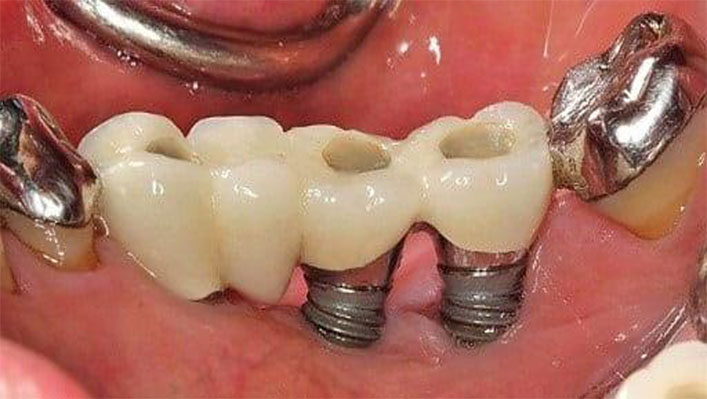

Problems Associated With Basal Implants

Many patients abroad search for “Are basal implants safe?” or “Basal implants vs conventional implants”. While basal implants are often marketed as quick-fix solutions for patients with poor bone, they come with significant drawbacks:

Mechanical Fixation Only (Osseo-Fix) – Basal implants do not truly Osseo Integrate with the bone. They only achieve a mechanical lock (osseo-fix), which poses long term problems since permanent stability requires biological Osseo Integration.

High Risk of Infection – Because of their design and placement in compromised bone, basal implants are prone to peri-implant infection

Cement-Retained Prosthesis – Most basal implants support cement-retained prostheses, making them very difficult to retrieve or repair when required. This creates problems if prosthetic adjustments are needed in the future.

Single-Piece Design – Basal implants are usually single-piece systems, which makes it extremely difficult to adjust angulation. In cases where implants must be placed at an angle (to avoid nerves or sinus), proper prosthetic correction at the gum level becomes impossible.

Poor Flexibility in Prosthetics – Limited prosthetic options result in compromised chewing efficiency and aesthetics.

Lack of Long-Term Clinical Evidence – Unlike conventional implants, basal implants lack robust international studies proving their survival and success rates.

All these reasons make basal implants a wrong choice for long-term implant success. For international patients seeking predictable, lifelong solutions, conventional implants using the CPBCCI protocol with multi-unit abutments remain the safest and most scientifically proven option.